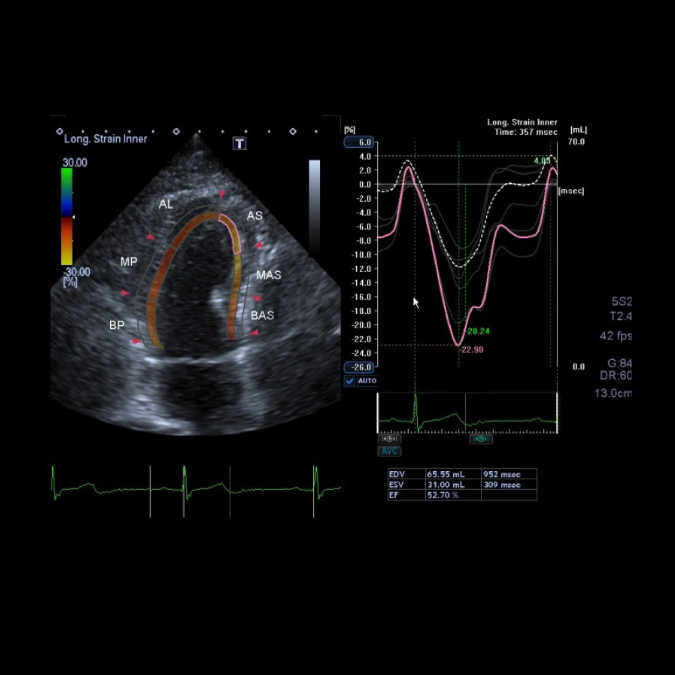

スペックルトラッキング法

心機能をより正確に評価する手段の一つとして、スペックルトラッキング法という手法があります。肉眼ではとらえることが難しい微細な壁運動の変化をとらえることで、診断や治療に生かす試みがなされています。たとえば、狭心症で左心室心筋の虚血障害は軽度の場合には肉眼ではとらえられません。そういう時にこの手法を使い、診断に重要な意味を持たせることができます(図1)。